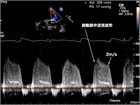

1. 心エコー検査(推奨度1)。